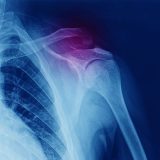

Shoulder Dislocation - Posterior or Anterior Fracture

Caused after the upper arm bone pops out of the shoulder socket. Can lead to pain, bruising, numbness, weakness or deformity.